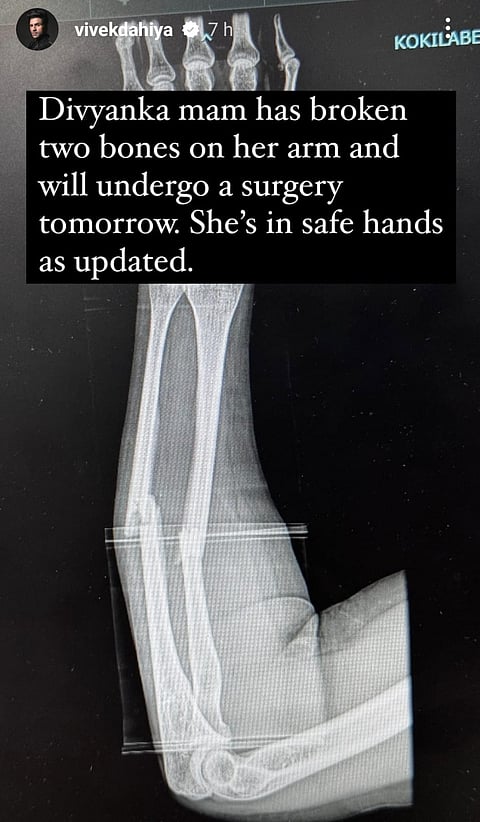

Television actress Divyanka Tripathi was rushed to a hospital after she met with an accident. The news has been informed by the actress' PR team and husband Vivek Dahiya. He informed her fans through his social media account that Divyanka had broken two bones on her arm and will undergo surgery today.